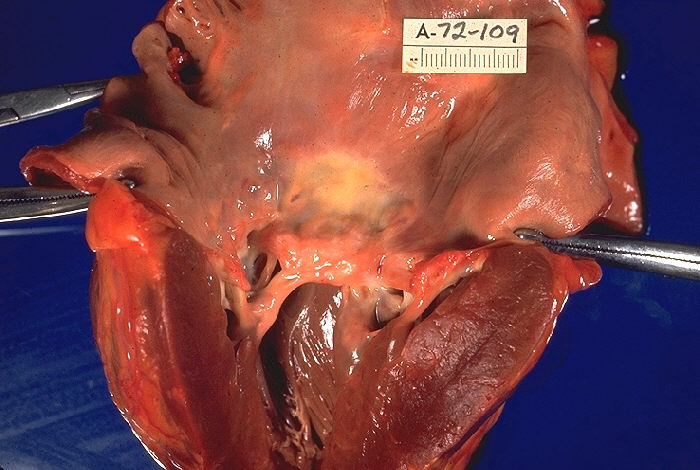

Gorączka reumatyczna to choroba zapalna, która rozwija się jako powikłanie po infekcji paciorkowcowej gardła (np. anginie). Może powodować zapalenie stawów, serca, skóry i ośrodkowego układu nerwowego. Nieleczona może prowadzić do trwałego uszkodzenia zastawek serca.

Echokardiografia, echokardiogram, echo serca lub po prostu echo, to badanie ultrasonograficzne serca. Jest to rodzaj obrazowania medycznego serca, przy użyciu standardowego USG lub USG Doppler. Echokardiografia stała się rutynowo stosowana w diagnostyce, zarządzaniu i obserwacji pacjentów z wszelkimi podejrzanymi lub znanymi chorobami serca. Jest to jedna z najczęściej stosowanych metod obrazowania diagnostycznego w kardiologii. Może dostarczyć wielu pomocnych informacji, w tym o wielkości i kształcie serca (kwantyfikacja wielkości komór wewnętrznych), wydajności pompowania, lokalizacji i zakresie uszkodzeń tkanek oraz ocenie zastawek. Echokardiogram może również dać lekarzom inne oceny funkcji serca, takie jak obliczenie rzutu serca, frakcji wyrzutowej i funkcji rozkurczowej. >>>